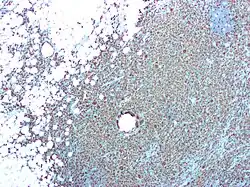

| CD68 immunostaining on this photomicrograph shows macrophages and giant cells in a case of xanthogranulomatous pyelonephritis. | |

Xanthogranulomatous pyelonephritis is an unusual form of chronic pyelonephritis characterized by granulomatous abscess formation, severe kidney destruction, and a clinical picture that may resemble renal cell carcinoma and other inflammatory kidney parenchymal diseases. Most affected individuals present with recurrent fevers and urosepsis, anemia, and a painful kidney mass. Other common manifestations include kidney stones and loss of function of the affected kidney. Bacterial cultures of kidney tissue are almost always positive.[25] Microscopically, there are granulomas and lipid-laden macrophages (hence the term xantho-, which means yellow in ancient Greek). It is found in roughly 20% of specimens from surgically managed cases of pyelonephritis.[10]